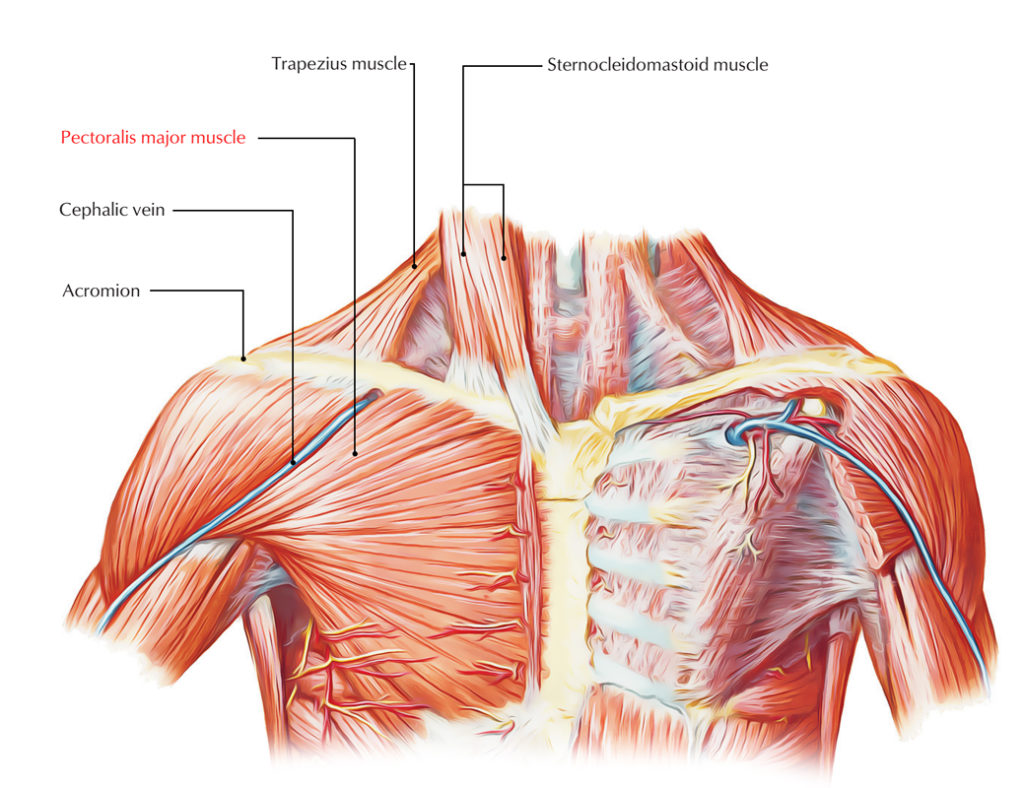

It is responsible for flexion, adduction, and internal rotation of. While you can’t truly isolate this muscle, you can increase its recruitment by performing. This is a small muscle that lies underneath the pec major.